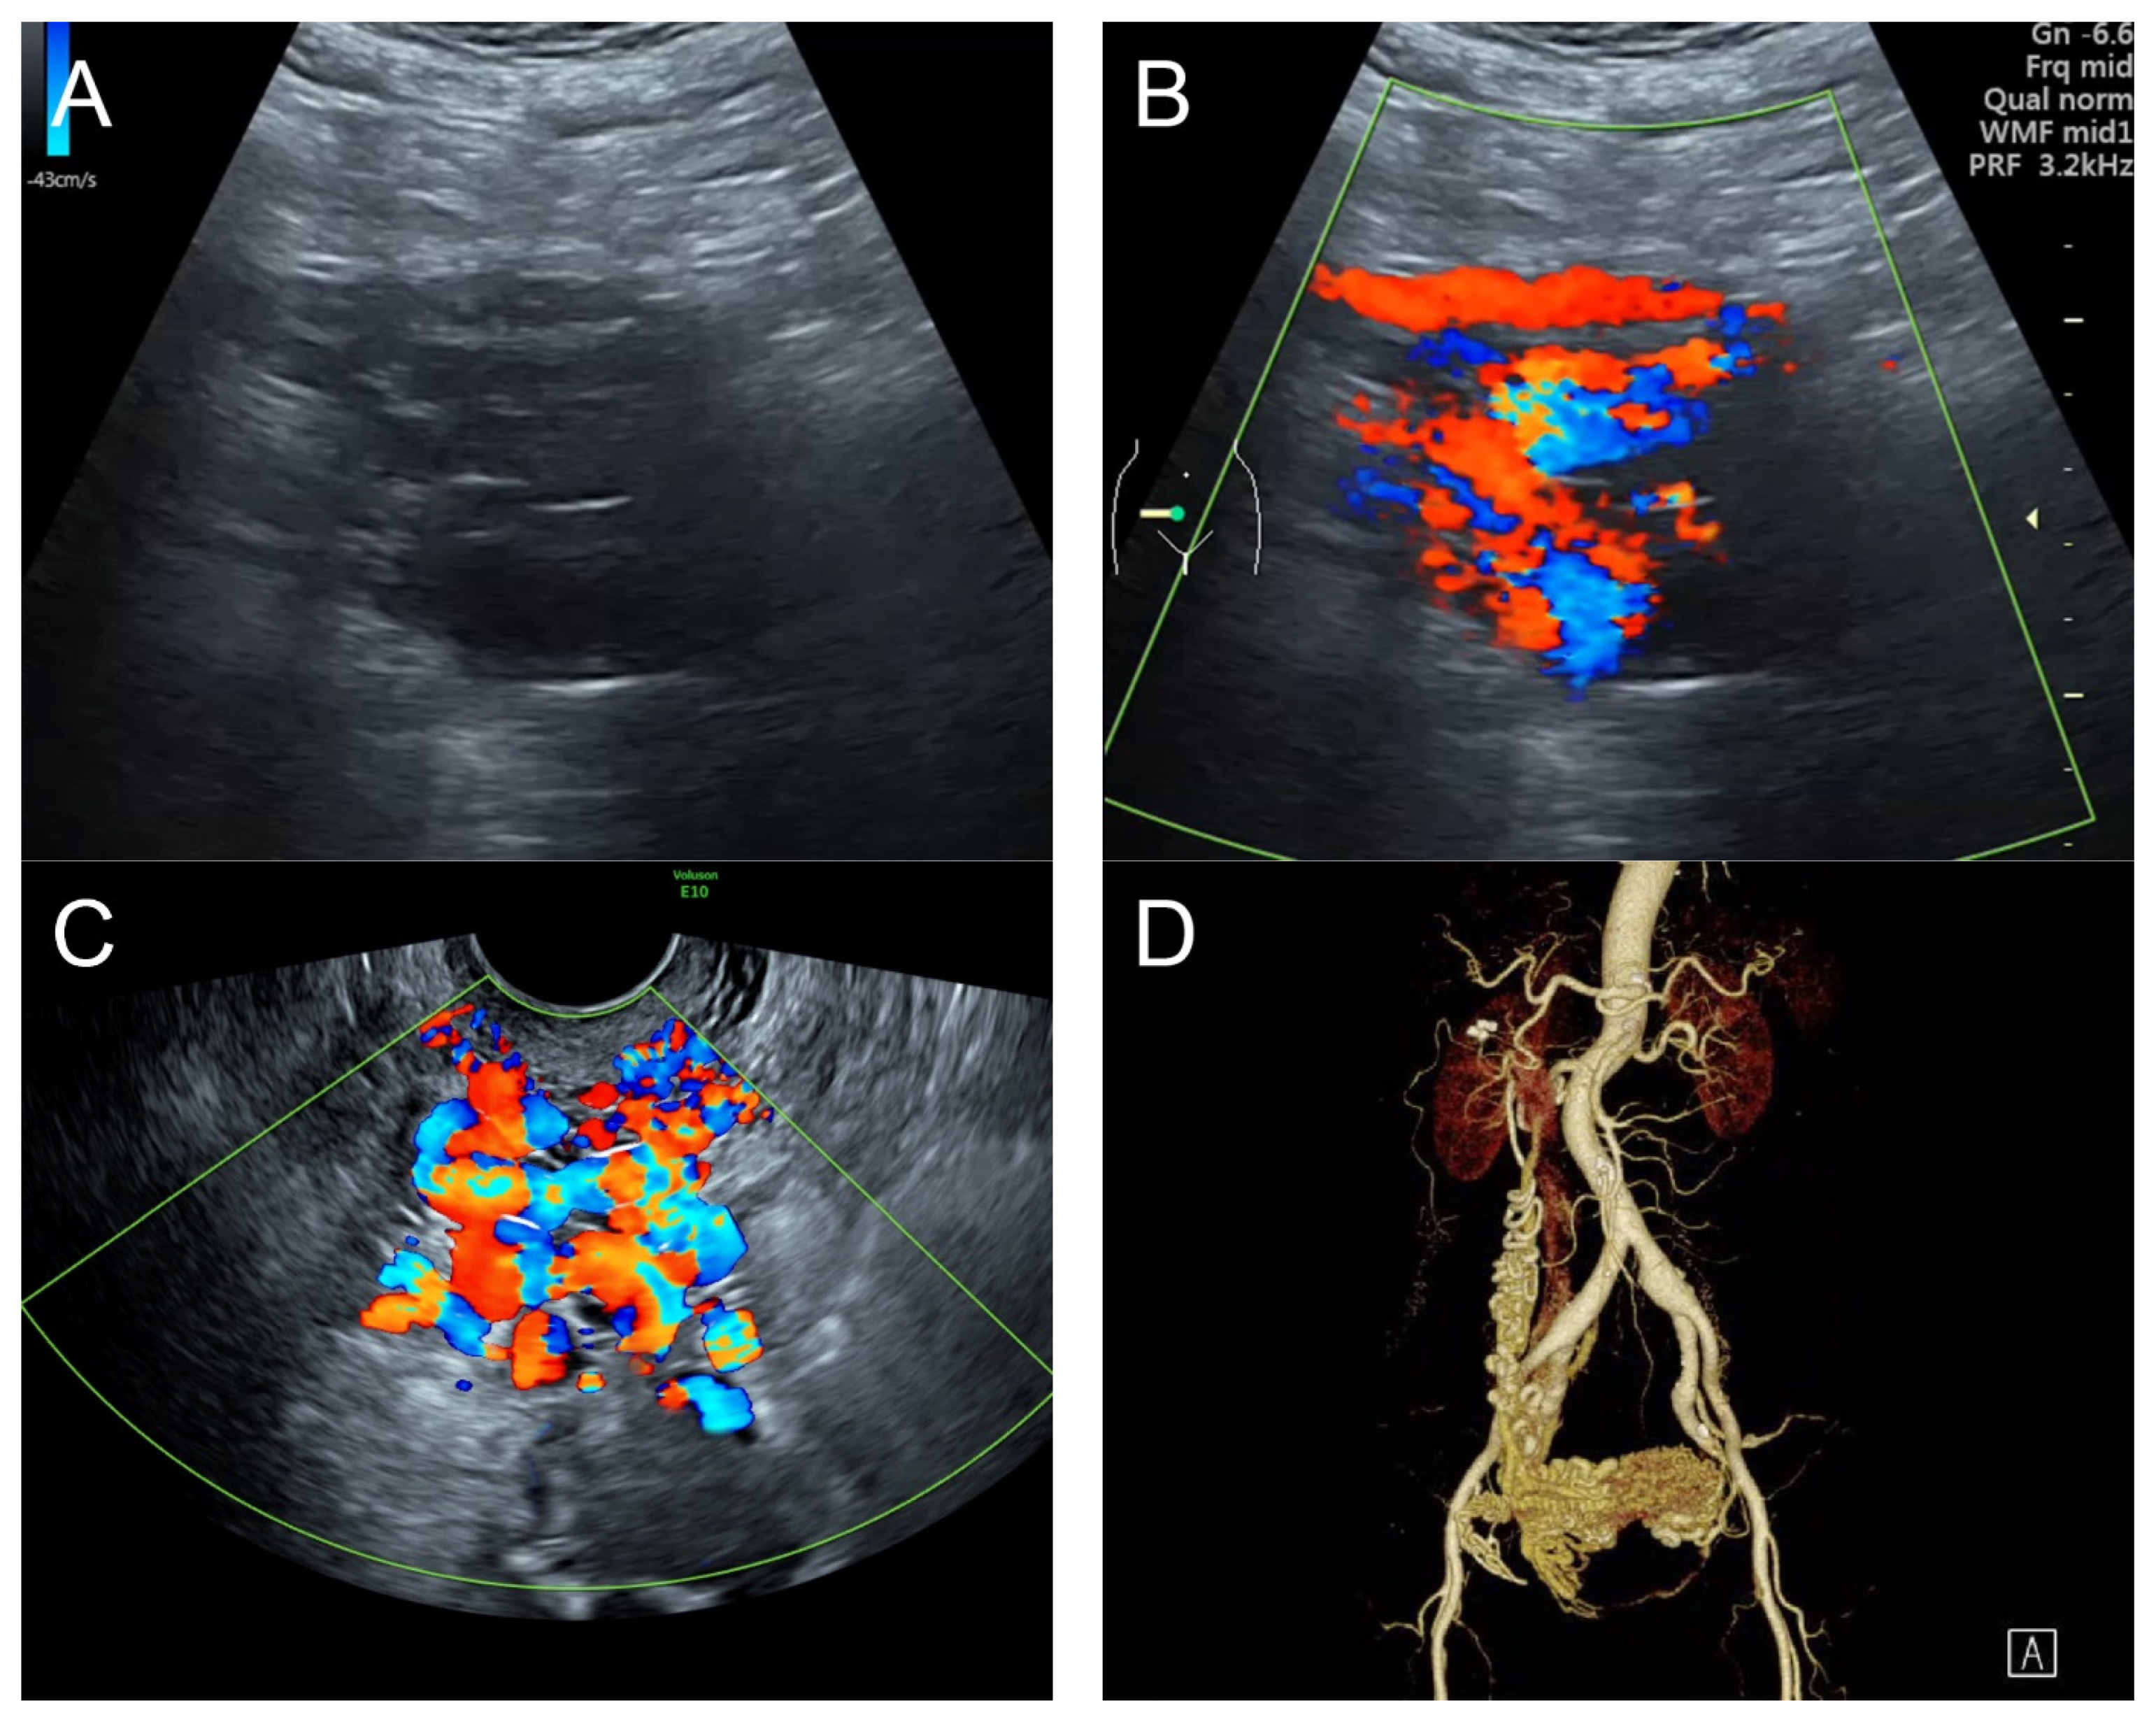

4. Case 3 (Figure 3)

Figure 3. (A,B) Grayscale ultrasound and color flow mapping transabdominal sagittal scans of the left lower quadrant showed a markedly enlarged and tortuous course of the left uterine artery, with a high peak systolic velocity of 60 cm/s in spectral Doppler waveforms. (C,D) Sagittal scans of the uterus in transvaginal grayscale ultrasound and color flow mapping showed numerous anechoic/hypoechoic tiny tubular structures within the myometrium, which tended to head to the endometrium in the direction perpendicular to the endometrial line. These tubular structures were scattered all over the uterus and strongly vascularized throughout the uterus. (E,F) Sagittal scans of the left adnexa in transvaginal grayscale ultrasound and color flow mapping showed a markedly enlarged and tortuous course of the left uterine artery.

Management: Initial therapy included blood transfusion and intrauterine tamponade with a Foley catheter balloon, resulting in less but continued bleeding. Abdominal CTA confirmed uterine AVM, and transcatheter embolization of both uterine arteries, using glue mixed with lipiodol, was performed, resulting in a reduction in bleeding. However, the follow-up abdominal CTA at 8 weeks after the procedure still showed significant residual AVM, and the patient still had abnormal uterine bleeding. Finally, a subtotal hysterectomy with bilateral salpingo-oophorectomy with resection of the AVM was performed, with satisfactory outcomes. Pathological examination confirmed the diagnosis of uterine AVM. Note that a subtotal hysterectomy, instead of a total hysterectomy, was carried out in order to minimize the risk of intraoperative excessive bleeding due to abundant vascularization in the lower uterine segment. On follow-up, the patient was healthy with no further abnormal bleeding at 2 years after the hysterectomy.